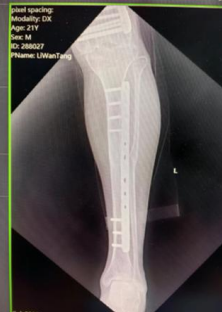

左股骨延长术后患者情况

在Ilizarov外固定支架的保护下,患者的运动功能被完好地进行了保留,且左腿每天都在加速“生长”。通过几个月的康复训练后,李先生再次到医院进行左股骨延长术后钢板内固定+拆除外固定支架术。术后唐继全查看患者左腿肢恢复情况,并叮嘱他一定要做好术后康复锻炼,早日恢复肌体功能。

Ilizarov骨延长手术中医师需要在左股骨截骨延长单边轨道外安装一个固定支架,就像盖房子的脚手架一样,通过钢针将外固定架和病损骨骼连为一体,医生会在骨骼上做适当的截骨,再慢慢延长使骨骼延伸生长。